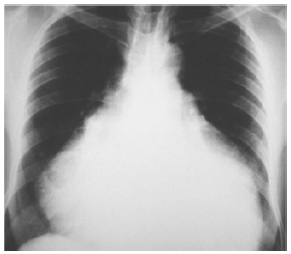

Paciente de 45 anos, sexo feminino, admitida em unidade de pronto atendimento com queixa de dispneia progressiva há 2 dias, com piora significativa até os mínimos esforços. Nega outros sintomas. Antecedente de neoplasia de mama, em acompanhamento irregular. Nega outras comorbidades. Nega uso prévio de medicações. Ao exame físico: vias aéreas aparentemente pérvias; frequência respiratória 26ipm, tórax com movimentos simétricos, murmúrio vesicular rude bilateralmente, som claro pulmonar a percussão, saturação periférica de oxigênio 88%; bulhas rítmicas e hipofonéticas, frequência cardíaca 120bpm, pressão arterial 70x40mmHg, pele fria, pegajosa, com tempo de enchimento capilar lentificado, turgência jugular evidente; aparente redução da amplitude do pulso e pressão arterial sistólica durante a inspiração; abertura ocular a estímulos dolorosos, emitindo palavras desconexas e localizando estímulos dolorosos, pupilas isofotorreagentes, sem déficit motor evidente. Trouxe radiografia de tórax realizada ontem em unidade primária de saúde (representada a seguir). Iniciado reposição volêmica com solução isotônica por acesso venoso periférico.

Qual é a conduta indicada?